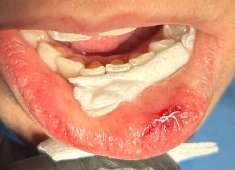

Il mucocele del cavo orale è la seconda lesione più comune. Nella fascia di età compresa tra 10 e 29 anni, il tasso di incidenza è più elevato. Il mucocele è caratterizzato da un accumulo di mucine. Ha una forma a cupola. Di solito hanno un colore bluastro. Il

mucocele si trova più comunemente sul labbro inferiore, seguito dalla mucosa buccale e dal pavimento della bocca. L'incisione tradizionale con bisturi e/o l'escissione chirurgica, la marsupializzazione, la micromarsupializzazione, l'iniezione di corticosteroidi, l'agente sclerosante, la criochirurgia, l'elettrochirurgia e il laser sono tutte procedure validate per il trattamento del mucocele in letteratura.

I laser a diodi forniscono una guarigione delle ferite e un tasso di recupero più rapidi rispetto ai loro rivali. Grazie alle sue

qualità antibatteriche e antinfiammatorie, questa terapia laser ha l'ulteriore vantaggio di migliorare la guarigione delle ferite senza infezioni o edema.

Le procedure laser-assistite sui tessuti molli presentano i vantaggi di un minimo sanguinamento intraoperatorio, edema e dolore postoperatorio, oltre a tempi chirurgici, cicatrici e coagulazione minimi.

La dimensione di un sito chirurgico determina se vengono utilizzate o meno le suture. Le procedure che comportano un'escissione piccola o significativa dei tessuti molli, l'esposizione dell'impianto con o senza taglio osseo, possono essere eseguite in pazienti con problemi di sanguinamento.

Questo caso è coerente con precedenti segnalazioni di escissione del mucocele utilizzando un laser a diodi.

L'enorme quantità di tessuto rimosso e il livello di comfort del paziente supportano ulteriormente il fatto innovativo che può essere utilizzato anche per il mucocele di grandi dimensioni.

I mucoceli della mucosa orale sono malattie tumorali benigne delle ghiandole salivari minori della mucosa orale. Si verificano più comunemente nella mucosa labiale. Possono essere causate da una rottura dell'epitelio della ghiandola che secerne saliva nello spazio extraghiandolare e forma una pseudocisti (mucoceli da stravaso) oppure da un blocco del flusso salivare dovuto ad una proliferazione epiteliale del dotto escretore che forma una cisti salivare (cisti da ritenzione).